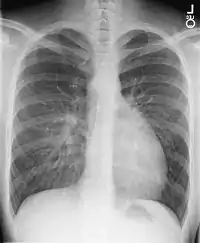

- الأشعة السينية على الصدر، الأشعة السينية على الصدر، تحول الأوعية الكبرى يظهر عادة صورة ظلية للقلب المنصف على أنها "بيضة على سلسلة"، حيث القلب المتوسع يمثل بيضة على الجانب والغدة الصعترية الضامرة من المنصف العلوي تمثل السلسلة.